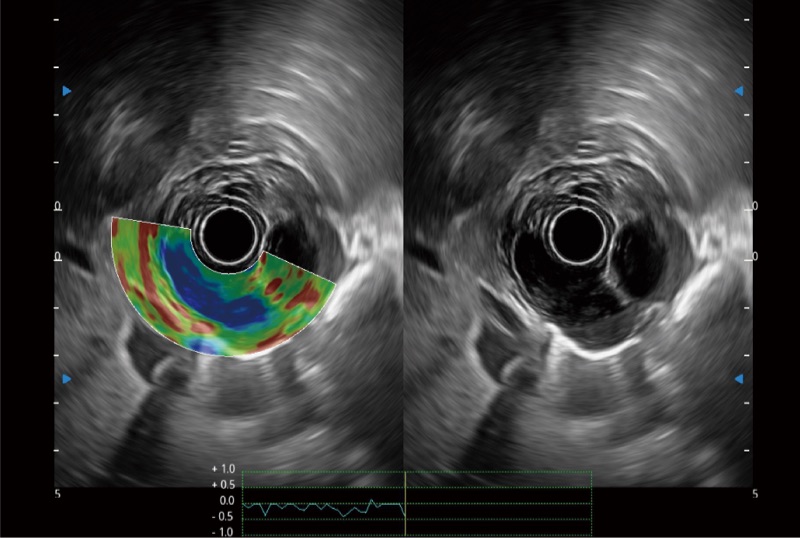

可人为将灰阶图像转变成彩色的显示方式,增强人眼对于不同回声强度的敏感度,主观上增加了图像分辨率

位移矫正技术

不可靠区域自动剔除

弹性定量分析软件